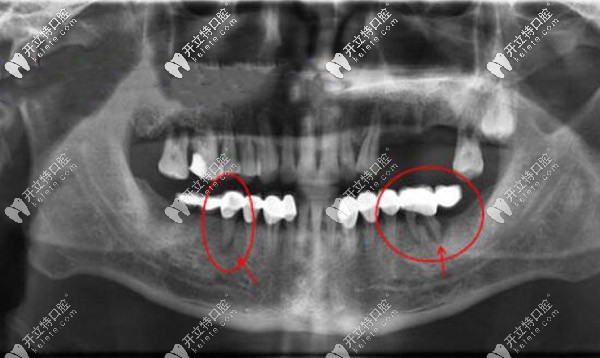

固定義齒是一種常用的治療方法。然而,對(duì)于需要安裝固定義齒的患者,他們常常會(huì)擔(dān)心固定義齒是否會(huì)對(duì)兩側(cè)牙齒的壽命產(chǎn)生影響,以及是否會(huì)對(duì)旁邊的2顆牙齒造成傷害。

千萬不要戴活動(dòng)假牙!我戴固定義齒已經(jīng)20年了,現(xiàn)在十分后悔,不知道牙齒的情況還能不能做滿口種植牙?